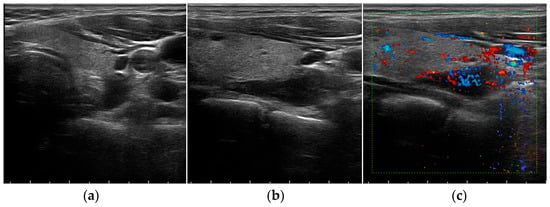

- Platz Batista da Silva, N.; Jung, E.M.; Jung, F. VueBox(R) perfusion analysis of contrast-enhanced ultrasound (CEUS) examinations in patients with primary hyperparathyroidism for preoperative detection of parathyroid gland adenoma. Clin. Hemorheol. Microcirc. 2018, 70, 423–431. [Google Scholar] [CrossRef]

- Pavlovics, S.; Radzina, M.; Niciporuka, R. Contrast-Enhanced Ultrasound Qualitative and Quantitative Characteristics of Parathyroid Gland Lesions. Medicina 2021, 58, 2. [Google Scholar] [CrossRef]

- Trimboli, P.; Castellana, M.; Virili, C.; Havre, R.F.; Bini, F.; Marinozzi, F.; D’Ambrosio, F.; Giorgino, F.; Giovanella, L.; Prosch, H.; et al. Performance of contrast-enhanced ultrasound (CEUS) in assessing thyroid nodules: A systematic review and meta-analysis using histological standard of reference. Radiol. Med. 2020, 125, 406–415. [Google Scholar] [CrossRef]

- Radzina, M.; Ratniece, M.; Putrins, D.S.; Saule, L.; Cantisani, V. Performance of Contrast-Enhanced Ultrasound in Thyroid Nodules: Review of Current State and Future Perspectives. Cancers 2021, 13, 5469. [Google Scholar] [CrossRef] [PubMed]